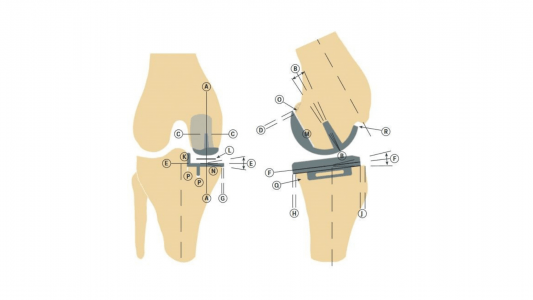

To Kέντρο Διαμερισματικής Αρθροπλαστικής Γόνατος του Kυανού Σταυρού–Euromedica Θεσσαλονίκης χρησιμοποιεί τα νεότερα και πιο εξελιγμένα παγκοσμίως μοντέλα διαμερισματικής αρθροπλαστικής, ενώ προσβλέπει και στον εξοπλισμό της με τις νεότερες γενιές τεχνολογικής υποβοήθησης (robotic knee), καθώς οι λύσεις που χρησιμοποιούνταν μέχρι πρόσφατα δεν κατάφερναν να ξεπεράσουν τα πολλαπλά σημεία ελέγχου που προσφέρουν ο ανθρώπινος εγκέφαλος και η εμπειρία της χειρουργικής τέχνης (Εικόνα 5).